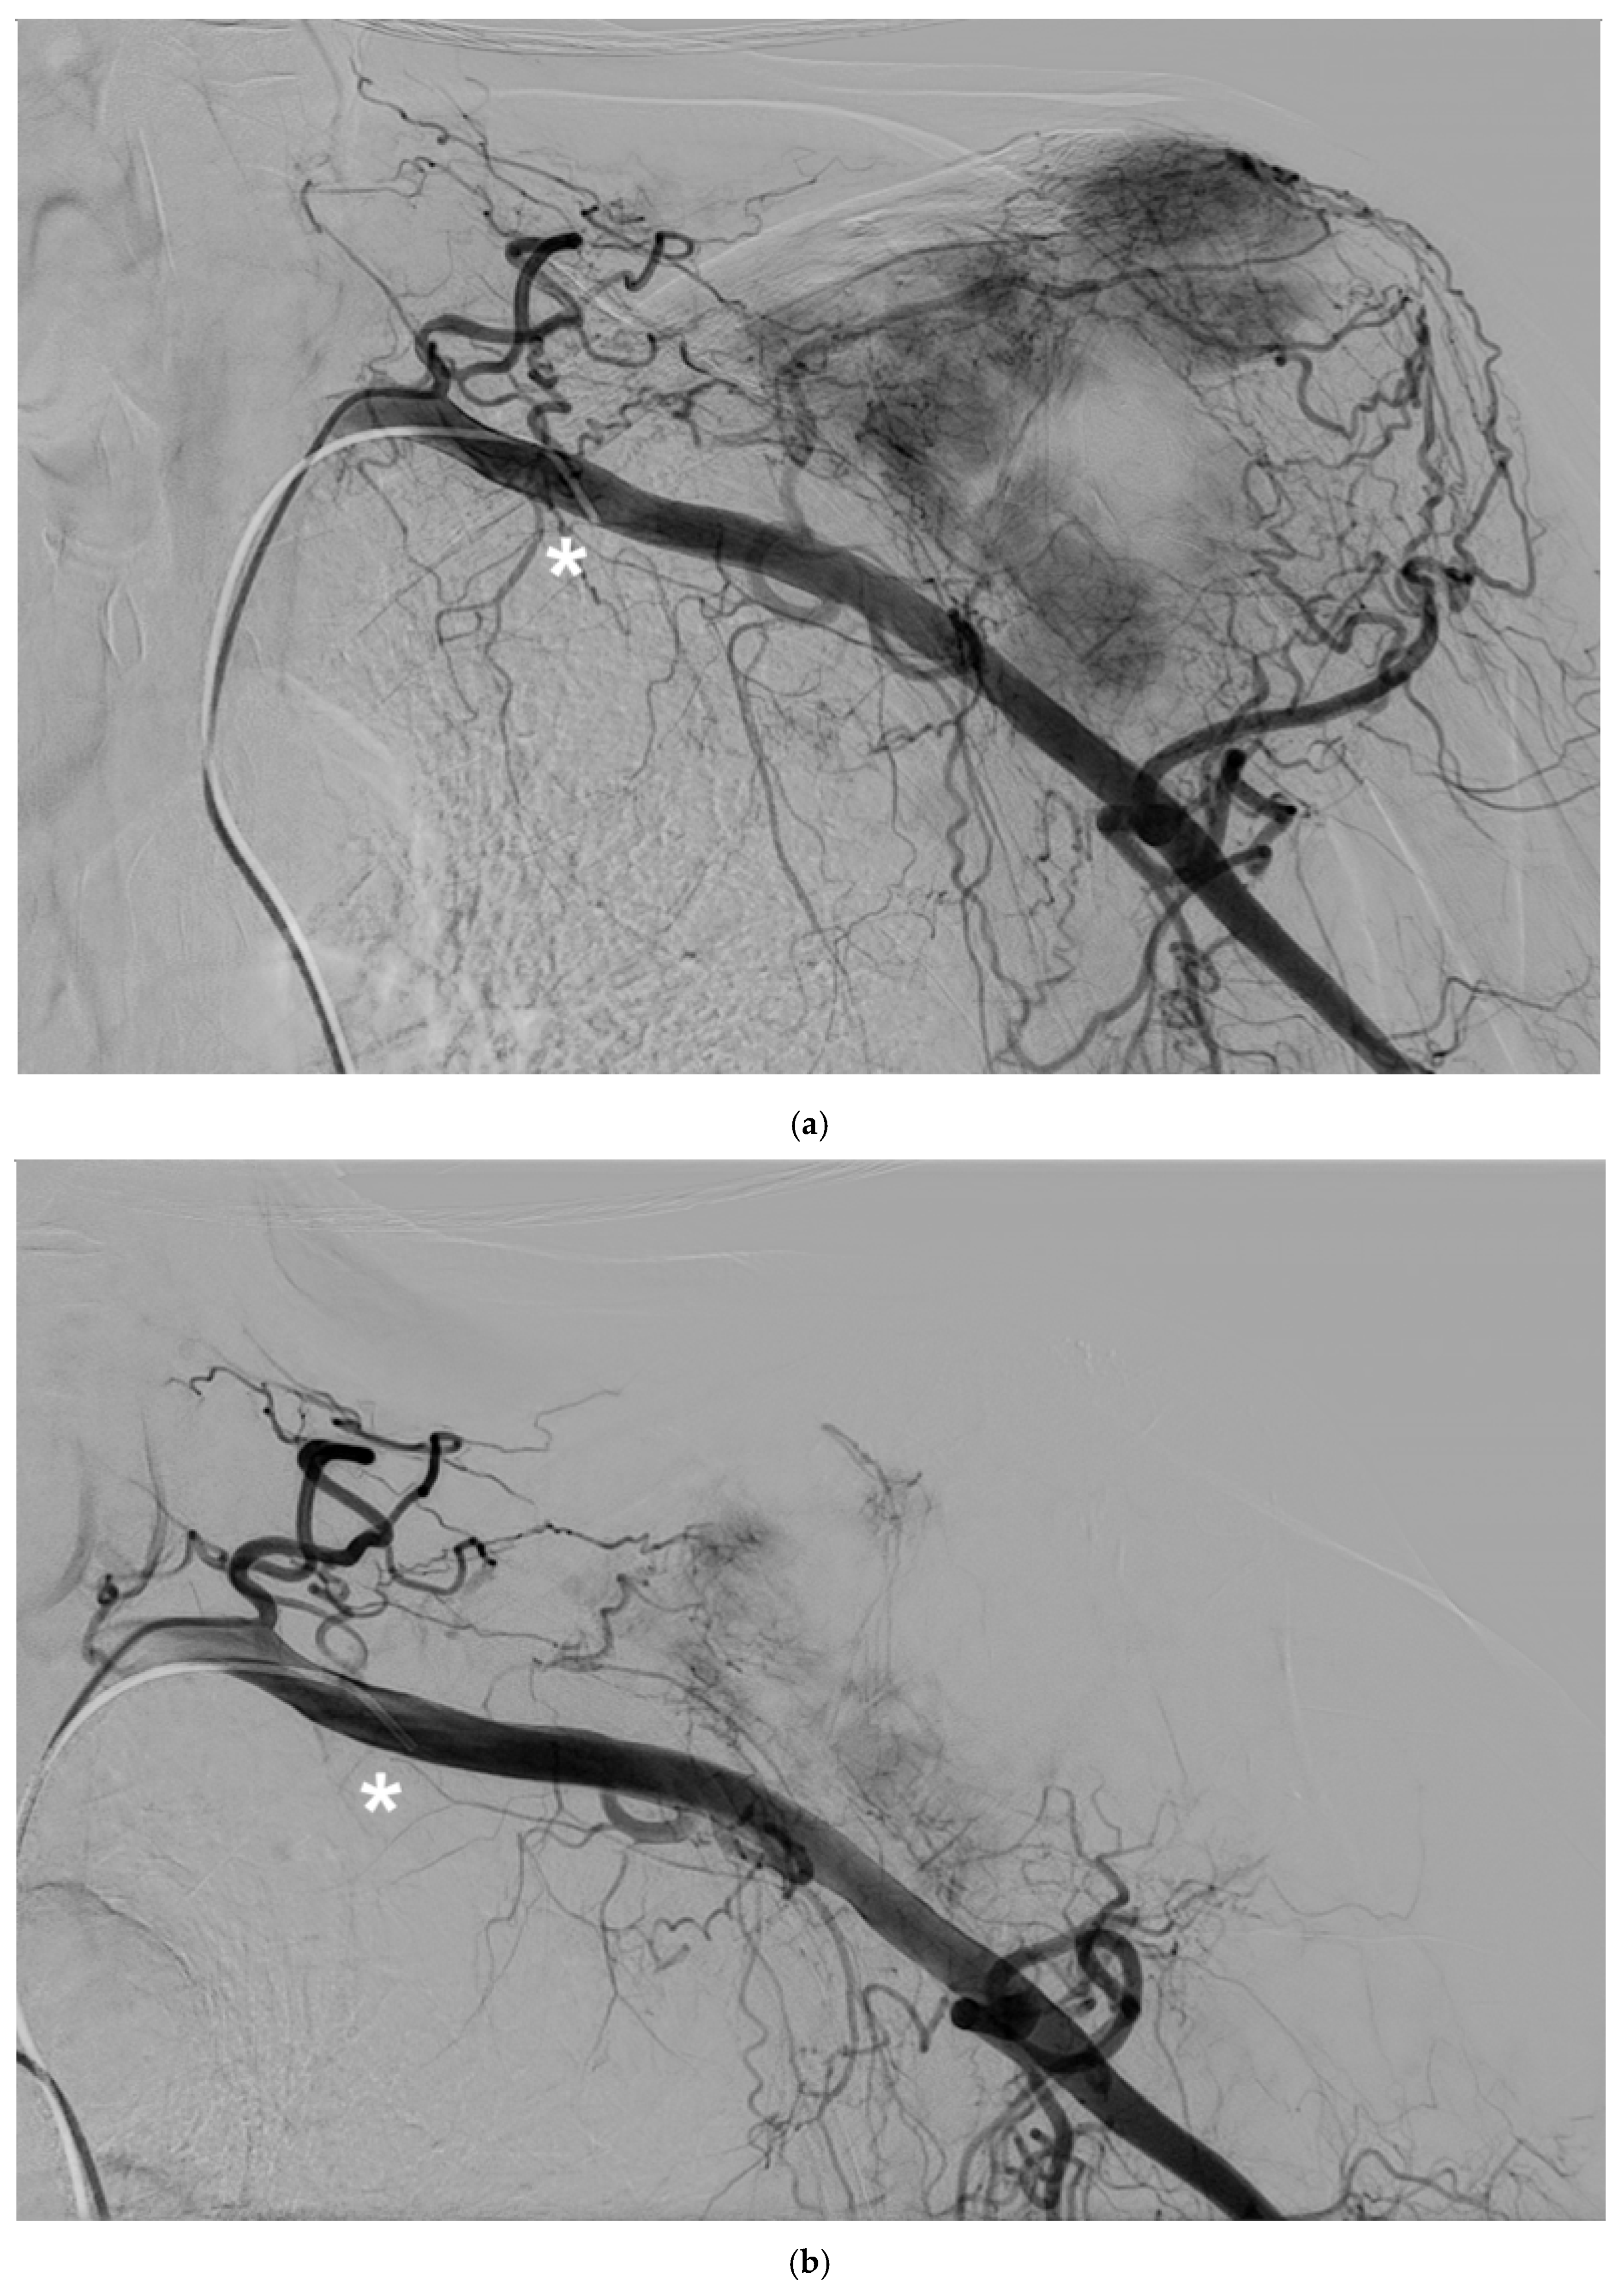

The study cohort included 14 patients (9 males, 5 females) with a mean age of 62 years (SD 10.2) who underwent palliative arterial embolization for scapular metastases. The primary arteries embolized were the circumflex scapular artery, the dorsal scapular artery and the thoracic-acromial trunk. A mixture of Glubran and Lipiodol in a 1:2 ratio was used for embolization, with an average of 1.1 mL (Range 0.5-1.5 mL) used per procedure (Figure 2).

Figure 2. A 62-year-old man with a single metastasis from lung cancer in the body of the scapula; a) arteriography performed with a 5F vertebral catheter positioned in the subclavian artery shows pathologic vascularization of the tumor and b) post-embolization arteriography performed from the same injection point, demonstrating near complete devascularization of the scapular lesion. C) Non-subtracted digital fluoroscopy demonstrating extensive presence of lipiodol/Glubran mixture in the embolized vessels (circle).